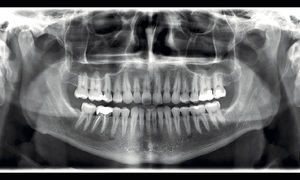

PAN X-RAYS

A Panorex X-ray displays a full view of your oral cavity, helping to diagnose problems with the jaw and more.